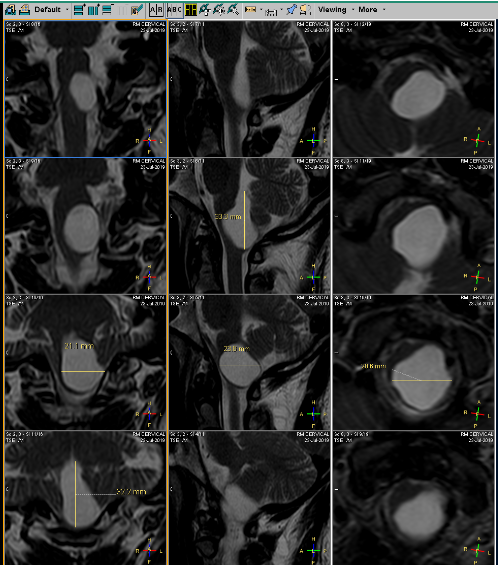

El 13 de agosto de 2019, ya con la resonancia de cráneo y los papeles del seguro, acudí con el doctor. Después de verlos me confirmó: "Es un tumor (quiste) benigno con el que nació. Se desconoce por qué se forman, pero una teoría es que son residuos de placenta que se quedan cuando se forma el producto en el vientre. Eso no es un tema, mi principal preocupación es su ubicación y tamaño mide: 3.3cm x 2.1cm x 1.7cm y se comunica con el cuarto ventrículo, y está obstruyendo el paso de líquido cefalorraquídeo a la columna". Me advirtió: "Va a ser un procedimiento muy doloroso, así que debes de estar consciente de ello". Llenó los papeles del seguro con carácter de urgente, con el diagnóstico: Tumor de comportamiento incierto o desconocido en el encéfalo y del sistema nervioso central.